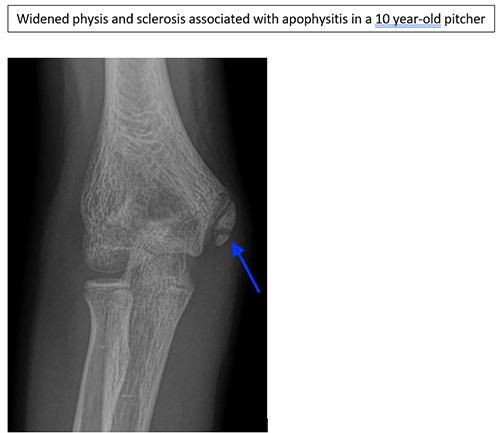

Medial Epicondyle Apophysitis

- Medial epicondyle appophysitis refers to a chronic inflammatory state where the muscles and tendons attach to the inside of the elbow

- This is an overuse injury as a result of repetitive strain across the medial elbow and associated with improper mechanics

- This typically presents with progressive medial elbow pain in overhead athletes 10 years or younger

- Pain in the late cocking and early acceleration phase is common as this is the highest valgus loads on the elbow

- X-rays typically demonstrate widened physis and sclerosis of the apophysis. Comparison films of the contralateral extremity can be very helpful for subtle differences